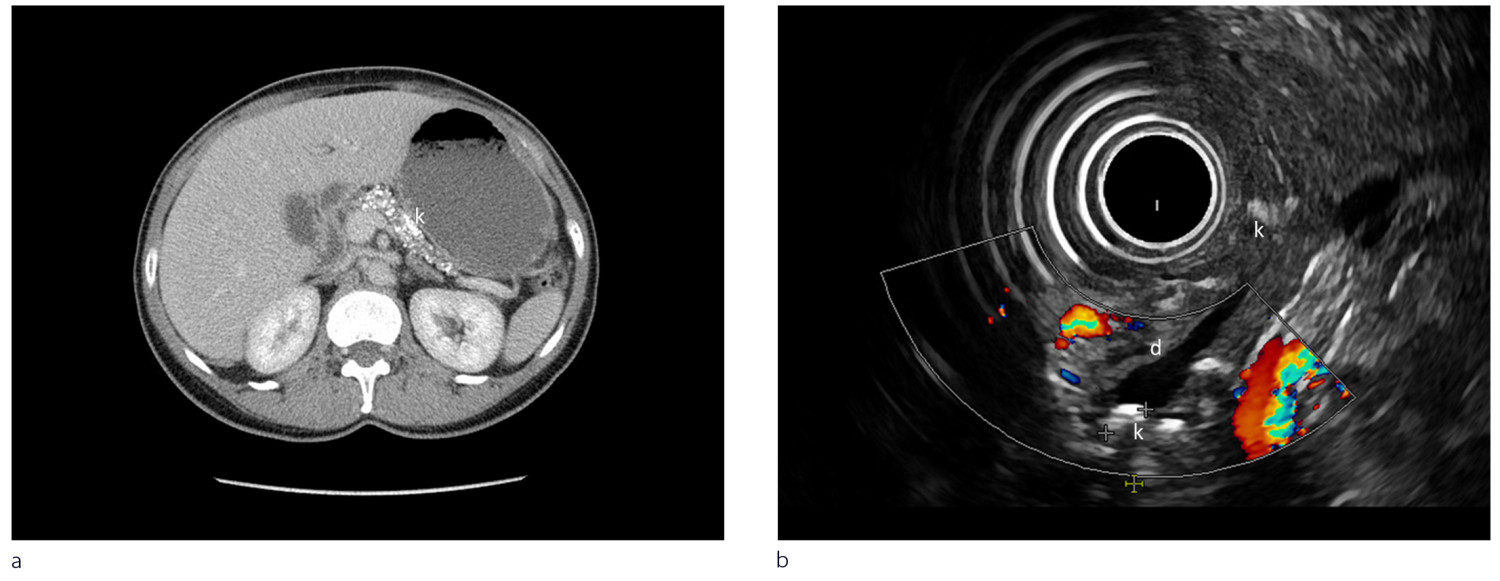

Radiologiske modaliteter som computertomografi (CT), magnetisk resonanstomografi (MR) og endoskopisk eller ekstern ultralydundersøkelse brukes til å påvise forandringer ved kronisk pankreatitt. Ved milde forandringer er endoskopisk ultralyd den mest sensitive metoden (1, 2). Fordeler og ulemper med de enkelte metoder med eksempler presenteres i figur 2 og ramme 3.

CT pancreas: CT-undersøkelse brukes i primærutredning og er gullstandard for å påvise forkalkninger ved kronisk pankreatitt. Undersøkelsen gjøres ved endring i symptombildet for å evaluere komplikasjoner som akutte pankreatitter, cyster, konkrementer eller malignitet